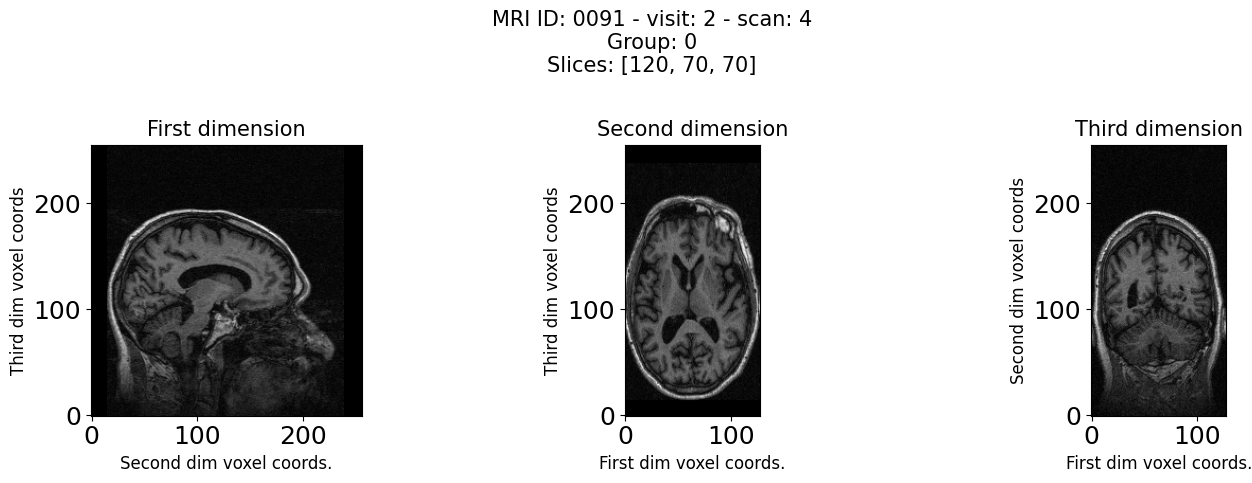

MRI images came in the form of NIFTI images (Cox et al., 2004). We converted these images into tensors by using NiBabel (Garyfallidis et al., 2014). We could have written a FATE compatible data loader to load the entire NIFTI images, but this would have required loading about 1 GB of data per batch with our batch size of 32, as each NIFTI image is around 30 MB. In the interest of efficiency, we chose to preprocess our MRI images into 256x256 JPG format for training purposes. We selected the 70th slice, 100th slice, and 125th slice. It is worth noting that writing a dedicated dataloader for NIFTI images would be more useful in a clinical setting. A cross sectional view of an MRI from our dataset is shown in figure 4.

Refer to caption

Figure 4: Cross sectional MRI Image